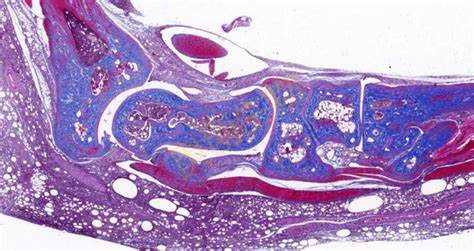

特殊染色是病理学和组织学中使用的一种染色方法,用于显示组织或细胞中的特定成分,这些成分在常规的苏木精 - 伊红(HE)染色中可能无法清晰地显示。以下是关于特殊染···...